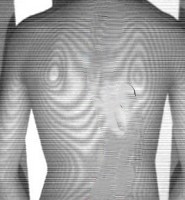

現在の学校検診は、検査者の経験に依存する視触診が中心のため、客観性に乏しく見逃しのリスクを内包しています。一部で導入されているモアレ法も、機器の普及や読影の属人性が課題となり、全国レベルでの検診精度の標準化を妨げる要因となっています。

体表面を高速に計測し、左右差やモアレ縞を視覚化。検診現場での簡便性と信頼性を追求しています。